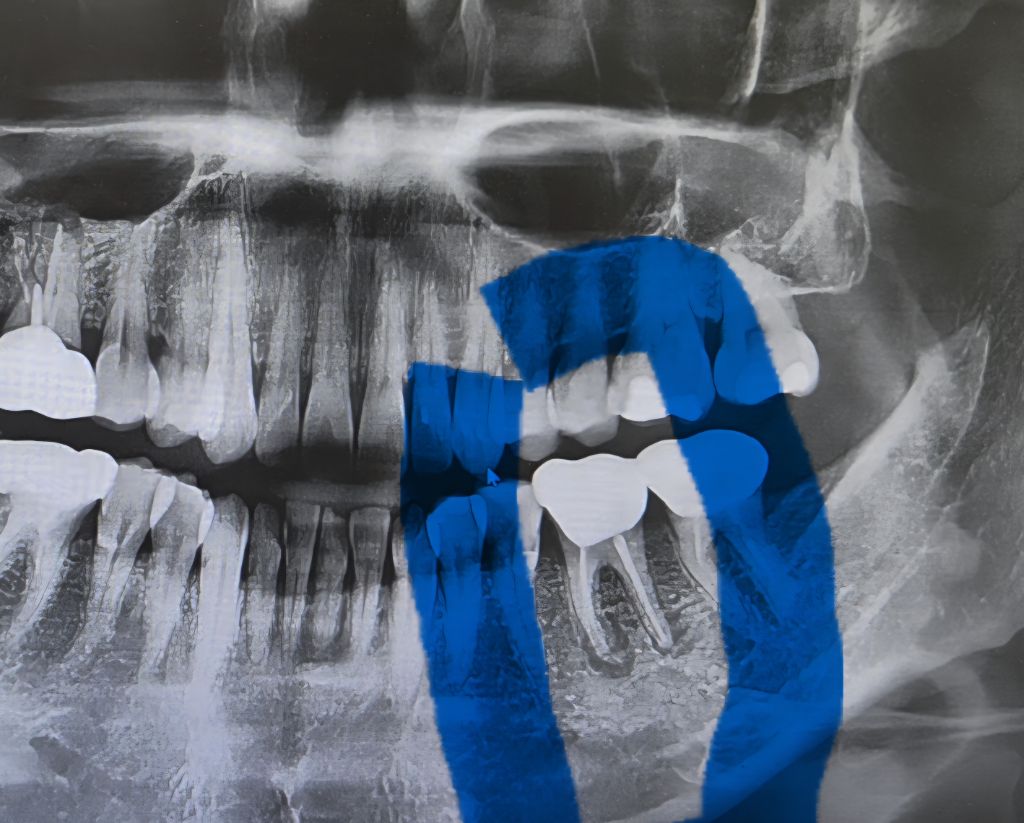

오래전 금으로 씌운 치아인데 뿌리에 염증이 있다고 발치해야 한다고 하네요

발치밖에 방법이 없을까요?

지금은 딱히 통증이 없는데 쓰는데 까지 써보고 발치해야 하나요? 하루라도 빨리 발치 하는게 더 좋을까요?